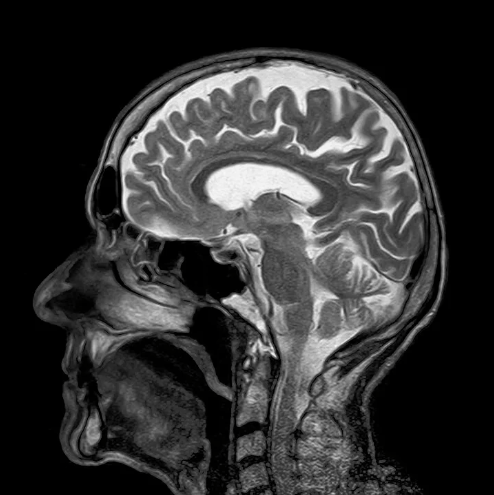

And to prove to you ladies that we do some dumb things, I have found scientific research. Don’t take advantage of this to bash on your man because he might not come home for one month. This is for you but don’t be using this against us. Are you ready? Ok, here we go. So the University of Oxford gathered around 121 participants, men and women from the age 4 to the age 40. They did an MRI scan to each and every one of them.

When the results came in, the doctors saw that for most women, they were all sharp and growing and maturing according to their age. However, when it came to men, some of us showed signs of continuous maturity even at the age of 40. So some of us, keep maturing until 40. That explains a lot. That’s why women are sharper than us and they tend to be smarter than us because we keep growing up until we are forty. That’s why people say that life starts after the ’40s.